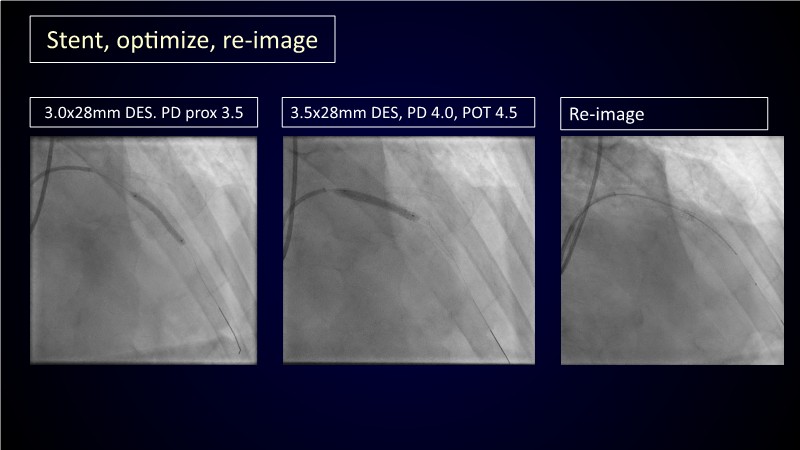

Calcified coronary lesions are a major challenge in PCI. This PCRGulf-GIM 2025 session showcases a complex case with intravascular imaging, highlighting how IVUS 123 guides each step.

From planning the procedure and understanding calcium distribution, to lesion preparation with modern modification tools, and post-PCI assessment to confirm stent expansion and detect complications, this session demonstrates practical, imaging-driven strategies.